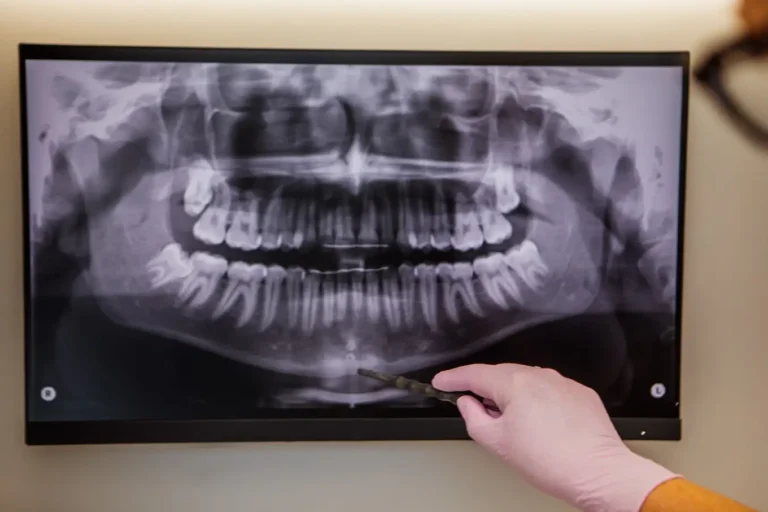

Tomografia zębów to zaawansowana metoda diagnostyczna, która umożliwia uzyskanie precyzyjnego obrazu jamy ustnej. Dzięki niej specjaliści oceniają stan zębów, kości szczęk oraz tkanek miękkich. Technika ta jest…